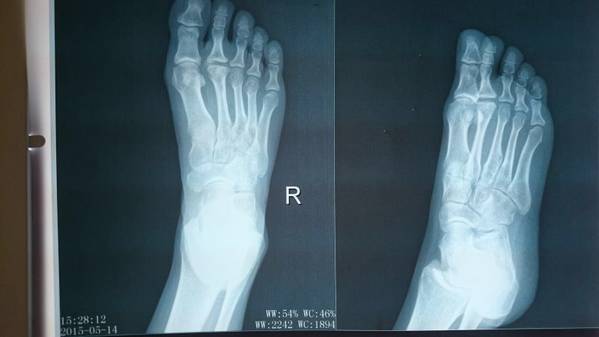

今天有医生问我这个病例怎么办

赶紧查阅资料:

这个疾病是第二跖骨头坏死,又叫Freiberg病

常用的治疗方法是第二跖趾关节清创跖骨头修整术、第二跖骨头切除关节成形术

一般不做关节融合术

对于早期患者可以考虑行第二跖骨颈截骨,跖侧关节面翻转到远端